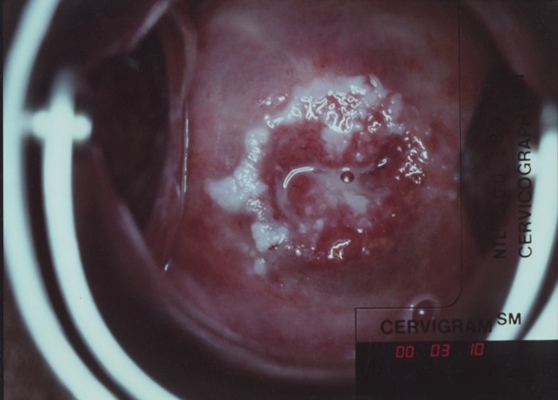

子宮頸癌圖片

宮頸癌

宮頸癌

宮頸癌

宮頸癌

宮頸癌

宮頸癌

宮頸癌

宮頸癌

宮頸癌

宮頸癌

宮頸癌

宮頸癌

宮頸癌

宮頸癌

宮頸癌

宮頸癌

宮頸癌

宮頸癌

宮頸癌

宮頸癌